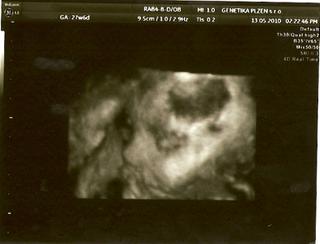

Dneska jsem byla znovu na tom 3D UTZ a miláček náš maličkej (zase tak maličkej není, dle MS 27+6 ale dle UTZ 29+0 a odhad váhy 1300g 😵 ) úžasně spolupracoval, takže teď jdu naskenovat fotečky a za chvíli vám je ukážu 😵

tak naskenováno 😵

Tak ty fotky jsou absolutně boží!!!!

Micha, fotečky Vojtíška jsou naprosto úžasné 🙂 Moc mu to sluší... To byl zážitek, co?